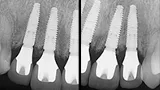

01 - Guided rehabilitation with implants in upper incisors region, after loss due to root resorption

Dr. Geninho Thomé and Dr. Sérgio Rocha Bernardes

Guided rehabilitation with implant in upper incisors region, after loss due to root resorption